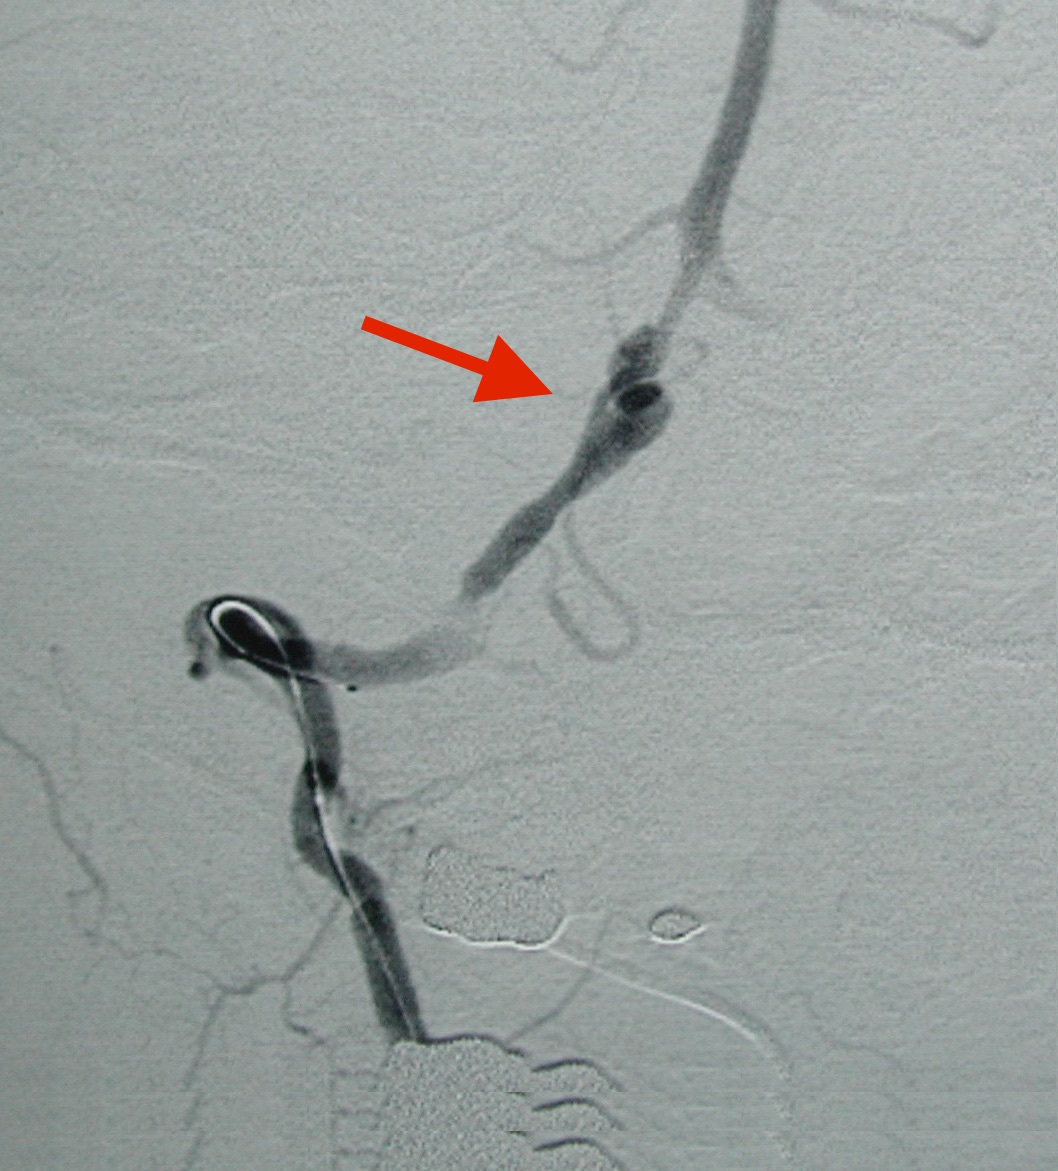

- 脳梗塞:特に椎骨動脈解離

未破裂でも特に椎骨動脈解離